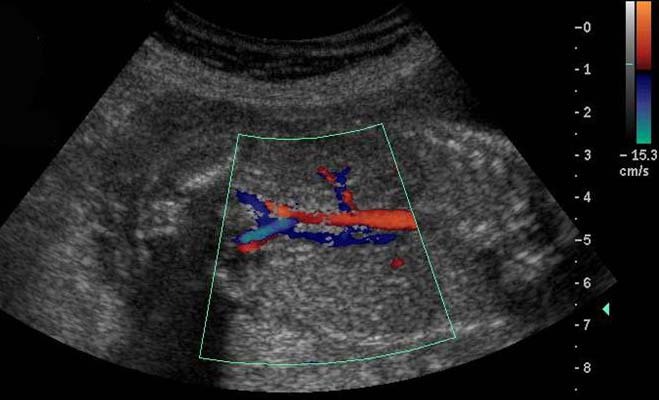

7 - Intérêt du Doppler couleur dans les pathologies de l'appareil urinaire

Visualisation de flux :

- vasculaire (angiographie)

- urinaires

Angiographie rénale :

- Le tronc de l’artère rénale est toujours vu, les segmentaires les sont souvent, les artères interlobulaires et arquées parfois.